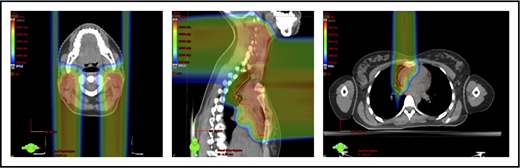

With regard to field arrangements, the PBSPT technique for an anterior upper mediastinal and lower neck target usually requires 1 (repainted) or 2 anterior fields. For more complex target volumes, targets can be divided into 2 or more parts (eg, neck CTV, mediastinal CTV, and axillary CTV), and a multifield plan can be used (Figure 5). For cases that involve lower (posterior) and upper (anterior) mediastinal targets, a combination of posterior and anterior fields can maximally spare the heart and lungs (Figure 6). For upper neck targets, lateral or posterior fields can avoid the oral cavity/salivary structures. For axillary targets, a posterior field can help to spare breast tissue. Although these various field arrangements can be used in PSPT, gradient matching is simpler in PBSPT when the fields overlap or oppose, obviating the need for feathering.

Plans for PBSPT with a single-field uniform dose and a gradient match, with anterior and posterior beams used to treat disease that involves the bilateral upper neck and the mediastinum (disease anterior to the right heart).